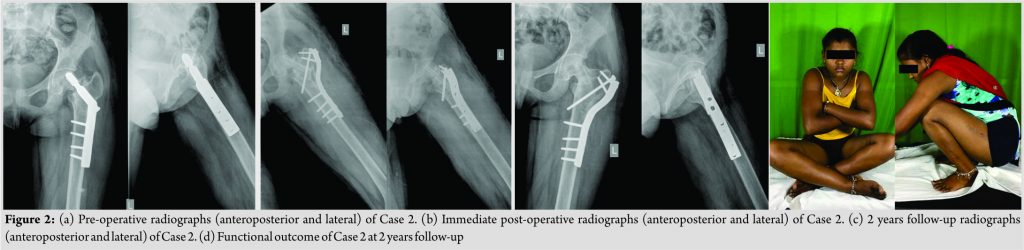

A 13-year-old girl presented with inability to weight bear on the left lower limb. 10 months back she had sustained fracture around the left hip following trivial fall and was confined to bed. 4 months after this fall, she underwent surgery of left hip (it could be verified from patient records that she had pathological fracture neck of femur secondary to the unicameral bone cyst and was treated by open reduction, subtrochanteric valgus osteotomy, and fixation with sliding hip screw). Following surgery, she continued non-weight bearing ambulation with crutches as any attempt to bear weight resulted in pain. Examination revealed the following ROM of the left hip: Flexion – 110°, extension – 5°, abduction – 30°, adduction – 20°, and internal and external rotations – 10° each. There was true supratrochanteric shortening by 2 cm. Radiographs revealed ununited transcervical fracture neck of the femur with sliding hip screw in situ and evidence of healed subtrochanteric osteotomy. There was no evidence of any focal bone pathology. Treatment given: Both cases were operated in the fracture table under general anesthesia. Hip joint was accessed through Watson Jones approach. All implants were removed. Cancellous bone graft harvested from ipsilateral iliac crest interposed at the pseudarthrosis site after freshening. Non-vascular fibular strut graft of appropriate length inserted through the sliding screw tract across the fracture site. Lateral based (1.5 cm) subtrochanteric wedge removed to valgise the femoral neck to a desirable extent (aimed at increasing the neck-shaft angle by 15°). Both the osteotomy and fracture fixed with contoured 4.5 narrow dynamic compression plate and screws. In Case 1, a cancellous screw could be passed into the neck across the pseudarthrosis. It was not possible in Case 2 as the neck was very narrow. Case 2 had an interfragmentary screw across the osteotomy site. Histopathological examination of the bone wedge removed revealed evidence of fibrous dysplasia in Case 1 and did not show any pathology in Case 2. Presumably, the cyst had healed though previous radiographs showing the cyst was not available. ROM exercises were started in the immediate post-operative period for both cases. They were made to walk non-weight bearing with axillary crutches for a period of 2 months after which they progressed to partial weight bearing as tolerated. Once evidence of full union was noted on the radiographs, they were progressively made to weight bear fully, and crutches were discarded. The fracture united uneventfully in both cases. The results and follow-up characteristics are summarized in Table 1 (Fig. 1 and 2).